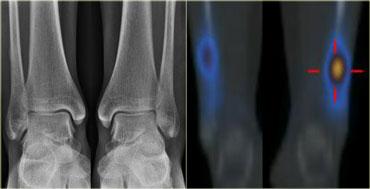

Gãy xương do stress hai bên đầu dưới xương mác: X-quang ban đầu và xạ hình xương tại thời điểm theo dõi 2 tuần.

Xương Mác

Gãy xương mác chiếm 10% các trường hợp gãy xương do stress.

Gãy xương do stress của xương mác thường xảy ra ở một phần ba đoạn dưới.

Hình bên trái là một vận động viên với triệu chứng đau ngay phía trên cả hai mắt cá chân, đau bên trái nhiều hơn bên phải.

X-quang chụp tại thời điểm khám không phát hiện bất thường.

Xạ hình xương 2 tuần sau cho thấy gãy xương do stress ở đầu dưới xương mác cả hai bên.

X-quang tại thời điểm theo dõi 6 tuần (không trình bày) xác nhận gãy xương do stress hai bên với xu hướng lành xương.